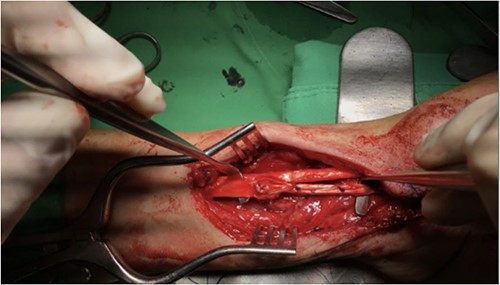

He was admitted to the hospital for further management and underwent plate removal, tenolysis and tendon graft reconstruction on 19 January 2021 (Fig. 2). The operation was successful, and the patient tolerated it well. No post-operative complications were observed. After the surgery, he was prescribed acetaminophen 500 mg four times a day and morphine 5 mg intramuscularly every 4 h as needed for pain control. Wound care with a wound dressing of Biomycin was also prescribed, and his vital signs and wound condition were closely monitored. Infection prevention was done with Cefazolin 1 g intravenously every 8 h.

The patient underwent plate removal, tenolysis and tendon graft reconstruction on 19 January 2021.

Post-operative photo showing removal of volar plate, tenolysis, release of flexor retinaculum and tendon graft reconstruction of FPL that were performed on 1 November 2022.